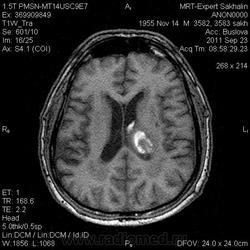

ID:53258

Онмк по геморрагичесому типу с образованием внутримозговой гематомы (подострая аза), прорывом в полость левого бокового и III -го желудочков.

Цель введения контраста наверное для исключения объема. Хотя. Наверное только динамика ответить на данный момент. Надо выносить в заключение весь диагностической ряд. Но больше похоже действительно на зона геморрагического НК. А сосуды не делали? Может имеет место венозное нарушение?

Танюша, не-а, в данном случае не имет место. Классика.